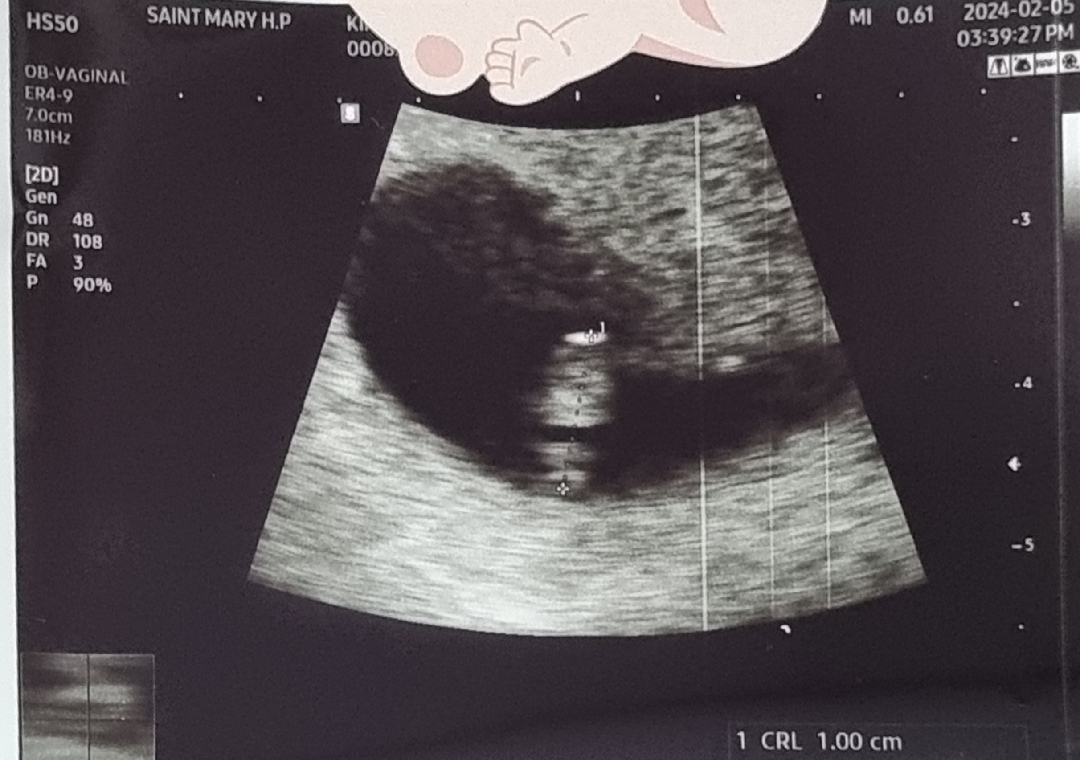

어제 하용이 보고왔어요

넘 흐리게 보이는게 아쉽지만 심장소리 들으러 간거에 의를 두고 갔다왔어요 남편도 잘 안보이지만 심장소리를 들으니 책임감이 더 생긴다고 하더라고요 이대로 잘 자라주길..하는 마음으로 다녀왔습니다 소변을 본다고 봤는데 대기가 길어도 그냥 있었더니 애기가 잘 안보이더라고요😂 맘님들도 참고하셔요 갔다 와서 생각났다는...ㅋㅋㅋㅋㅋㅋㅋ 소변보고 다시 보여달라고할걸 후회했슴돠